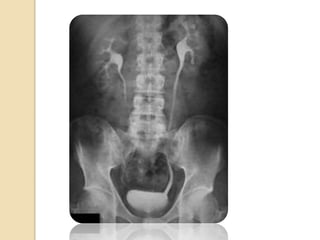

Pielografía intravenosa

Se realiza cuando el paciente tiene infección en la

vejiga y los riñones, y hay presencia de sangre en la

orina

Será necesario vaciar la vejiga inmediatamente antes

de que comience el procedimiento.

El médico inyectará un medio de contraste (tinte) a

base de yodo dentro de una vena en el brazo. Se

toman una serie de imágenes radiográficas en

diferentes momentos para ver la forma como los

riñones eliminan el tinte y la forma como se acumula

en la orina

Medio de contraste

Un medio de contraste es cualquier

sustancia que se usa para mejorar la

visibilidad de estructuras o fluidos dentro

del cuerpo

Pielografía intravenosa Se realizacuando el paciente tiene infección en la vejiga y los riñones, y hay presencia de sangre en la orina Será necesario vaciar la vejiga inmediatamente antes de que comience el procedimiento. El médico inyectará un medio de contraste (tinte) a base de yodo dentro de una vena en el brazo. Se toman una serie de imágenes radiográficas en diferentes momentos para ver la forma como los riñones eliminan el tinte y la forma como se acumula en la orina

• 32.

Medio de contraste Unmedio de contraste es cualquier sustancia que se usa para mejorar la visibilidad de estructuras o fluidos dentro del cuerpo